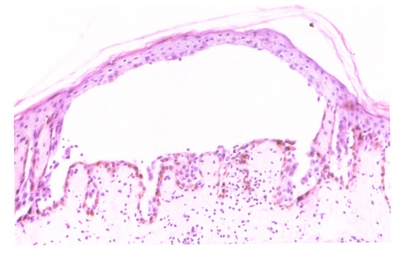

寻常性天疱疮组织病理象表皮内大疱